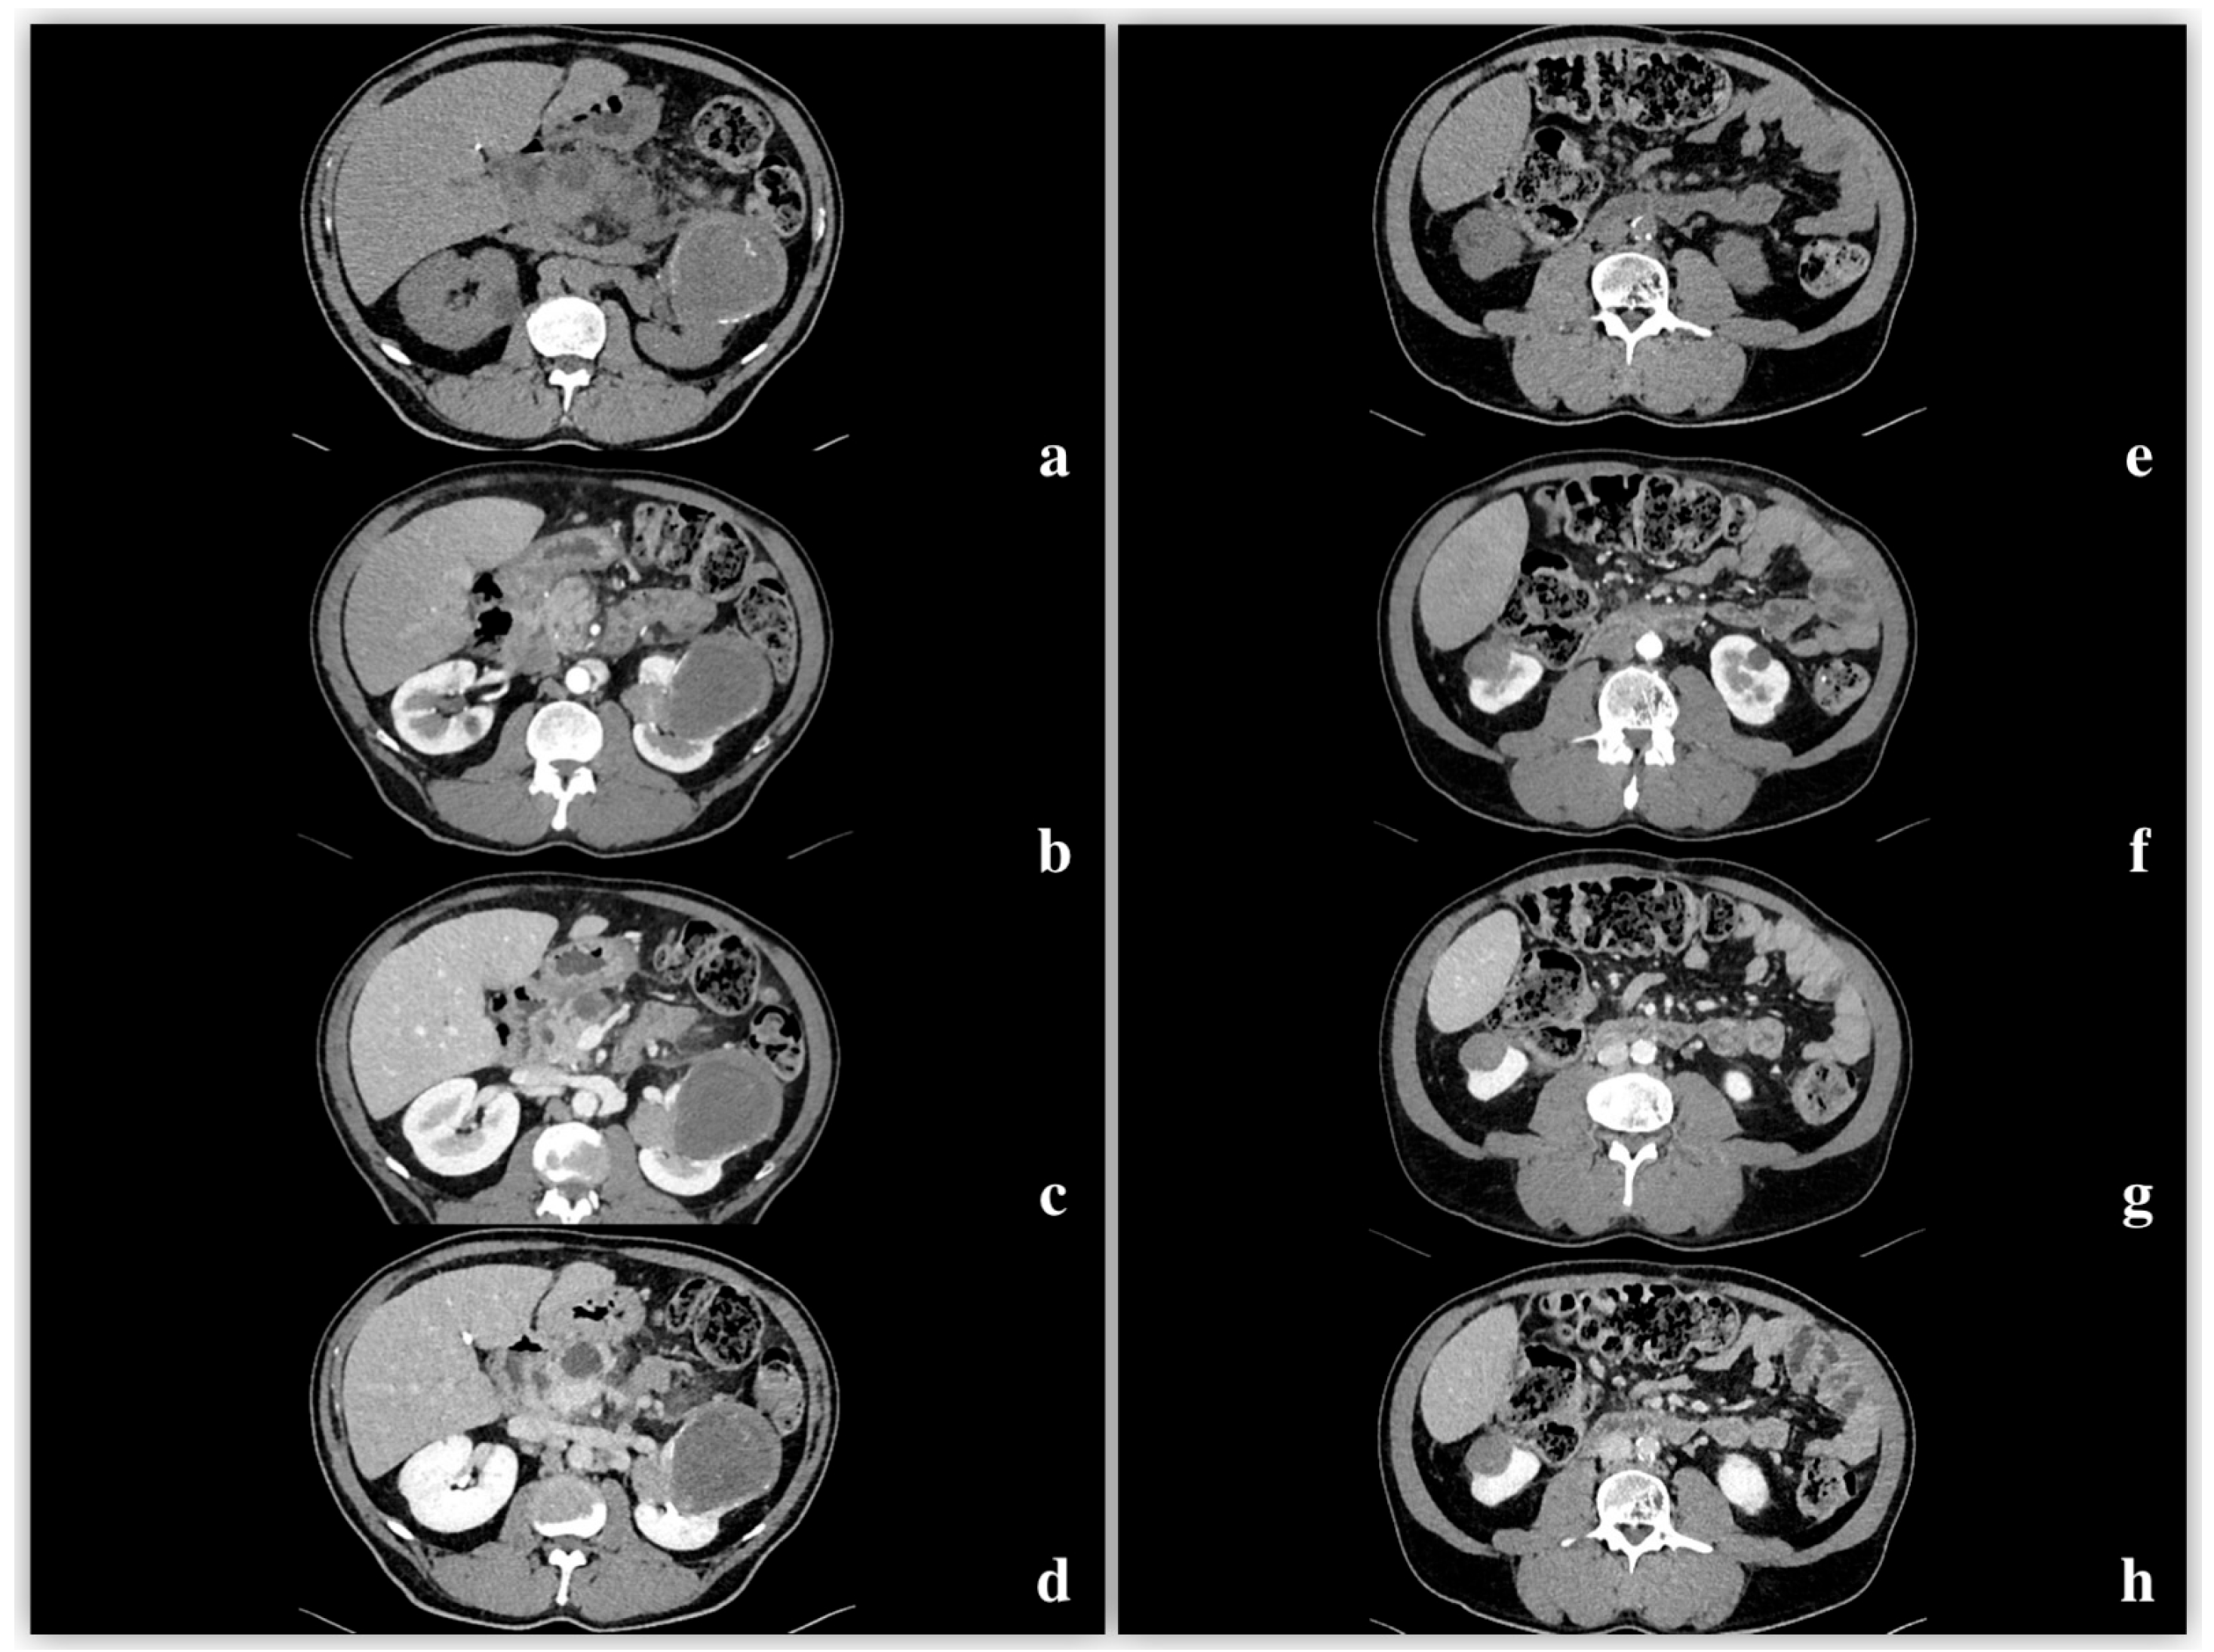

3.3. CT

Density and Contrast Enhancement

- Pre-enhanced phase: 30.3 ± 6.5 HU.

- Arterial phase: 47.2 ± 12.4 HU.

- Venous phase: 64.6 ± 17.3 HU.

- Delayed phase: 61.8 ± 14.5 HU.